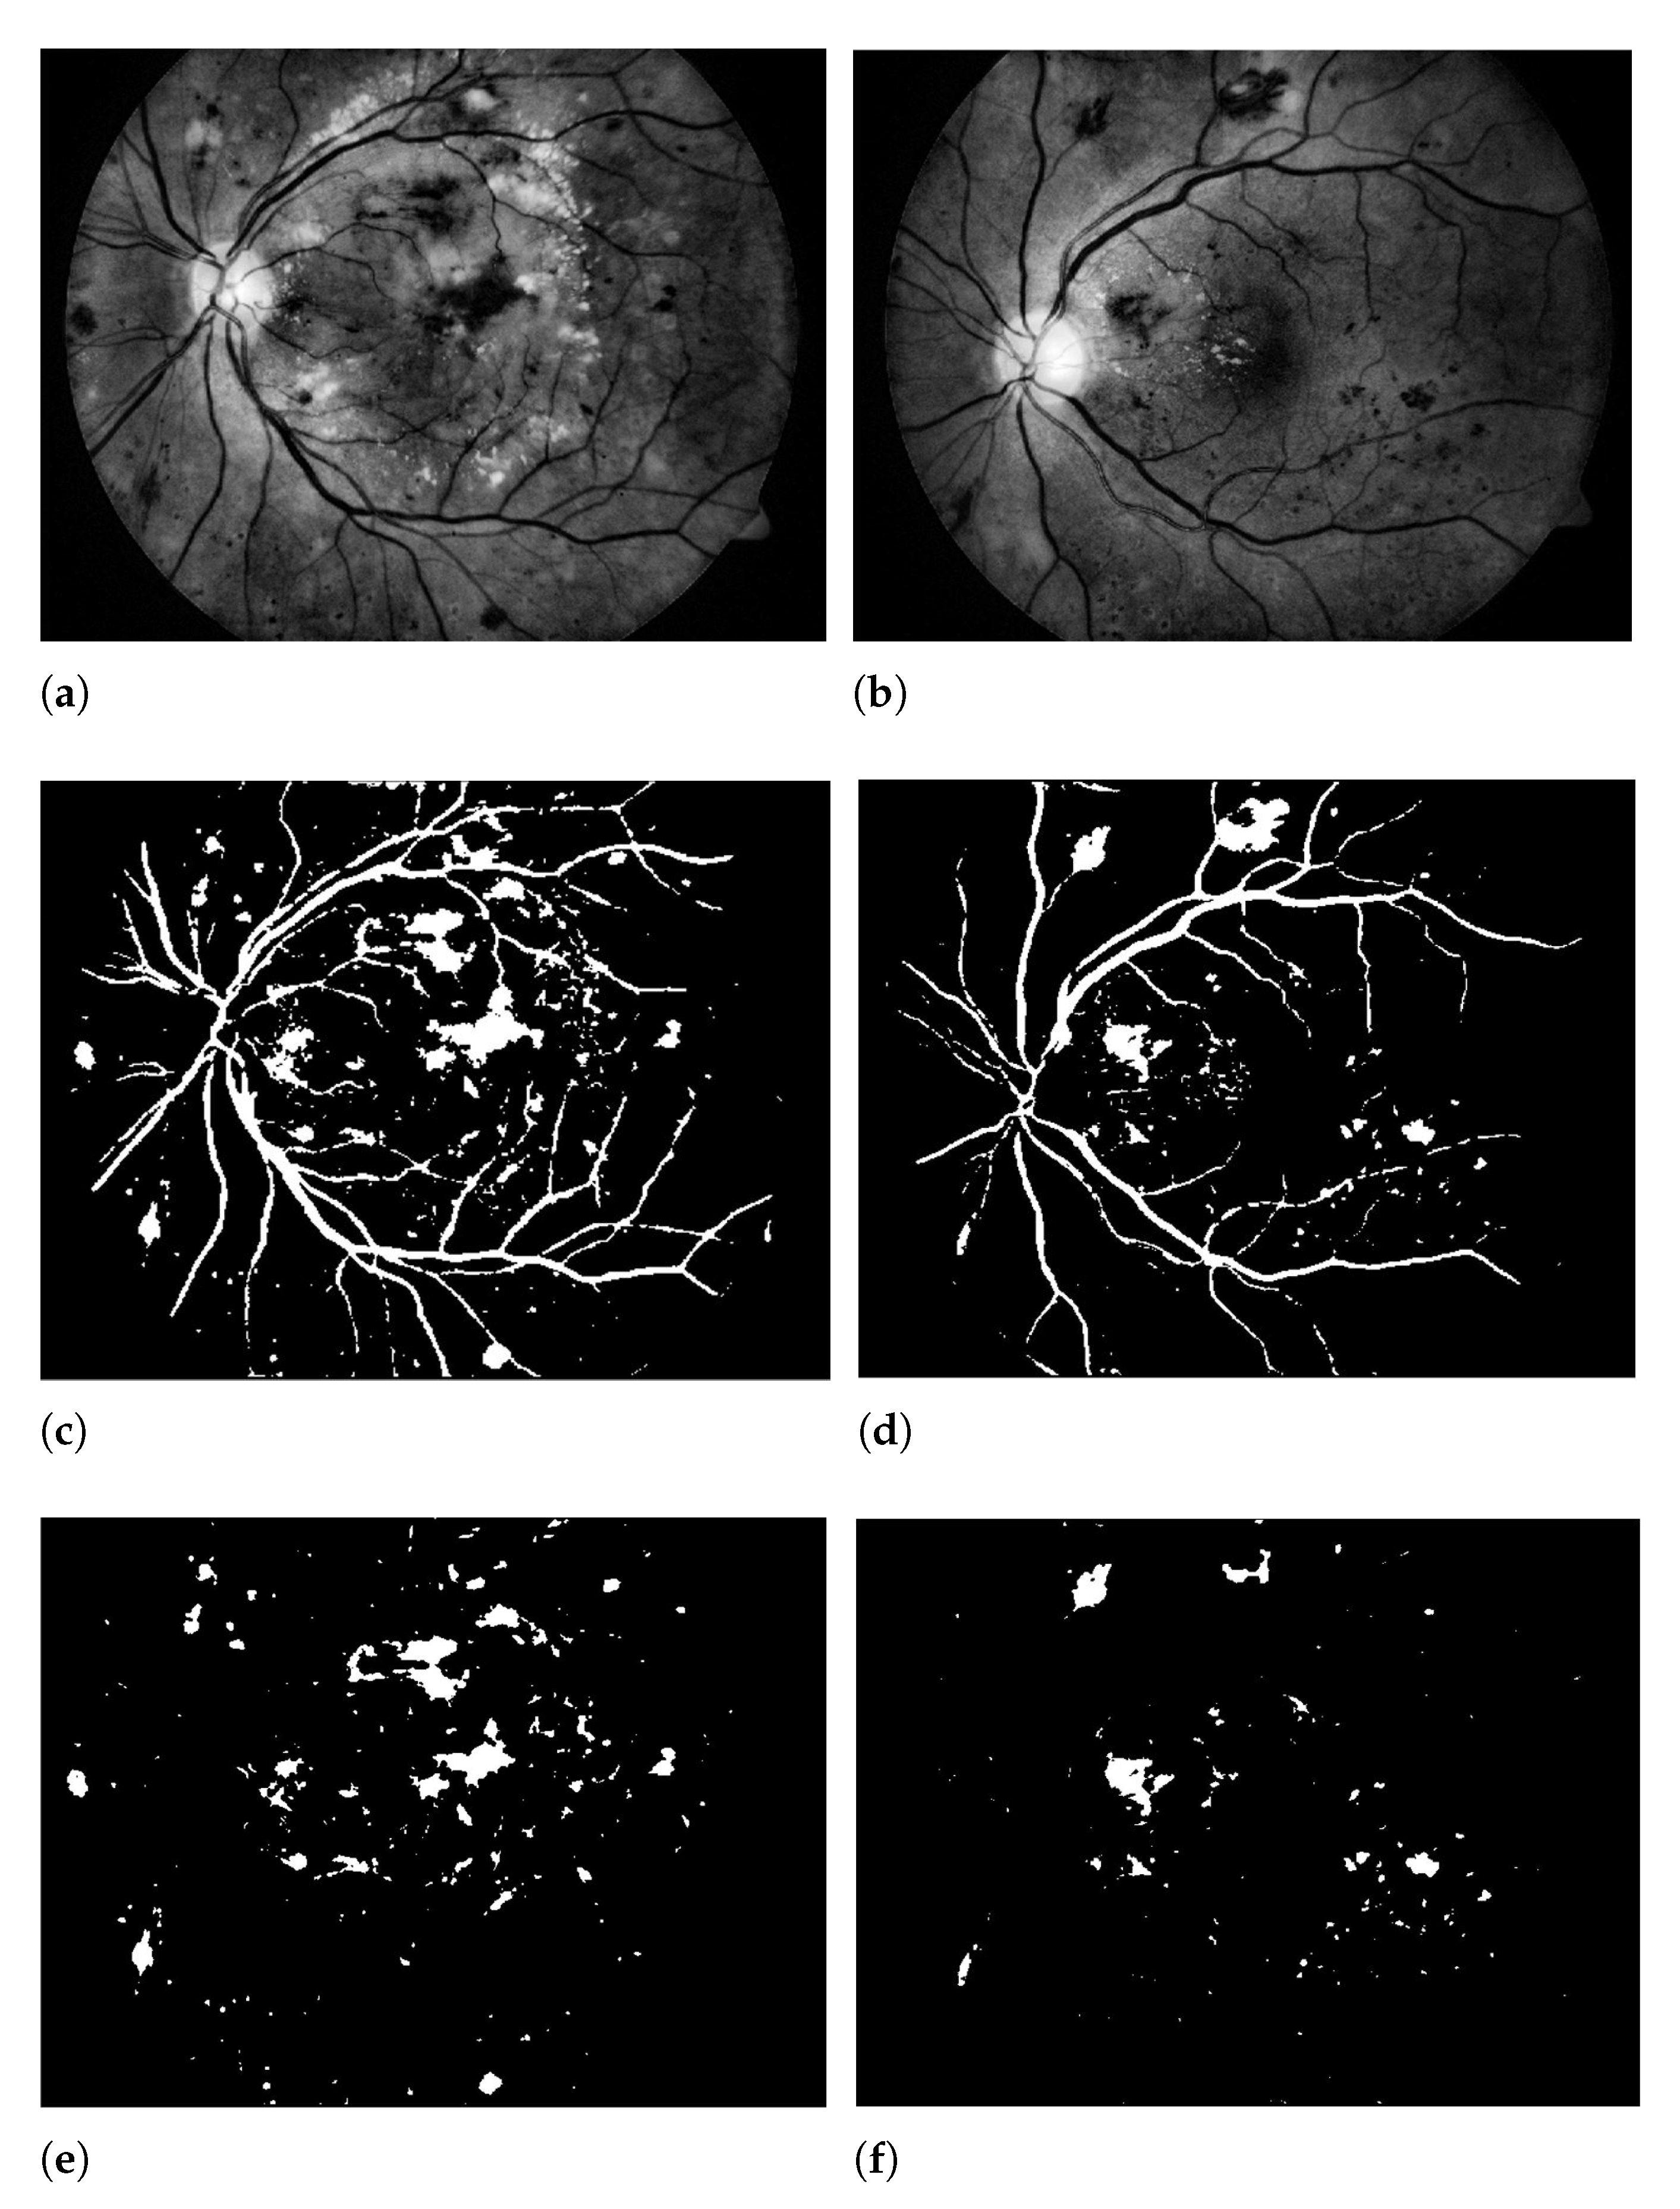

3.1. Green Channel Extraction

3.2. Contrast Enhancement

3.3. 3D CNN Based Segmentation Model

4.3. Results and Discussion